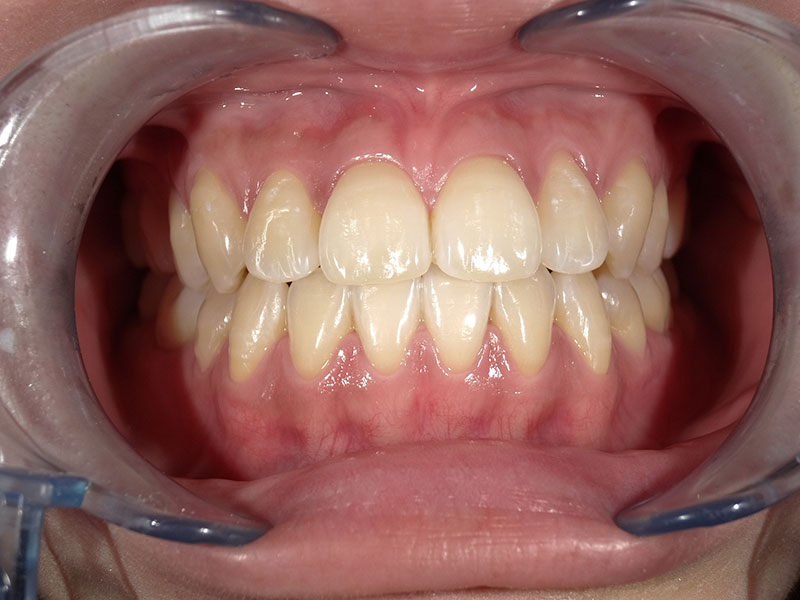

ホワイトニング症例

治療前

Before

治療後

After

年齢 26

性別 女性

主訴 歯を白くしたい